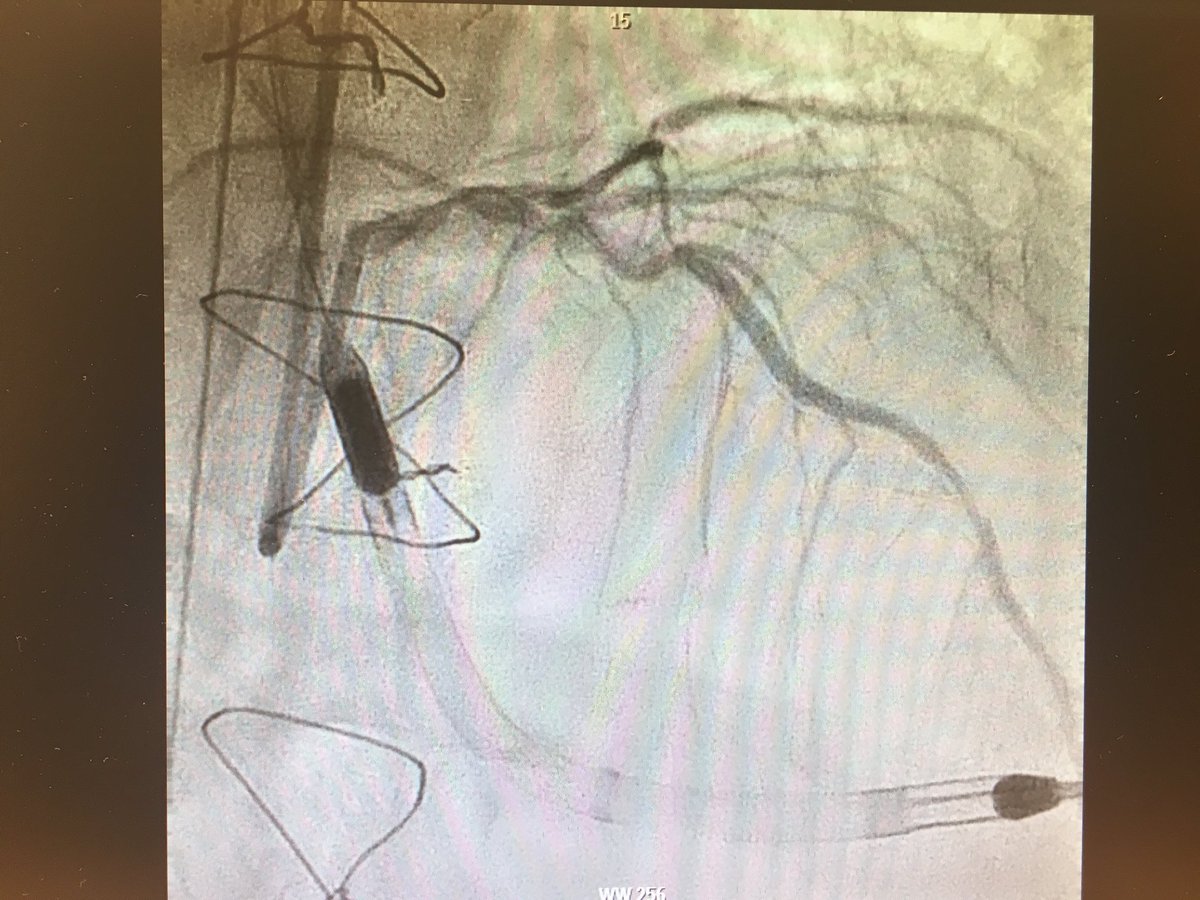

#CHIPcase 74yo male, LM+3vd, LVEF 17%, previous non-functionant CABG. Previous inferior MI without inferior viability. Actual NSTEMI with cardiogenic shock. Sent to our centre for Complex PCI @foroic @belcid7 @sbrugaletta @mmamas1973 @shci_sec @jedicath @hect2701 @Xavi_Carrillo7